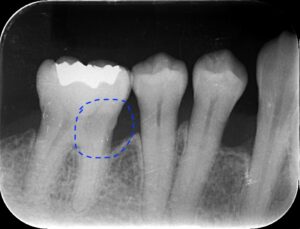

コーヌスデンチャーとは残っている歯に冠のような金属を被せてその上にさらに金属を被せる

2重の冠でできた入れ歯になります。茶筒の原理で固定されるため安定感が高く、審美性や装着感に

優れています。ドイツで開発されたテレスコープデンチャーの一種です。